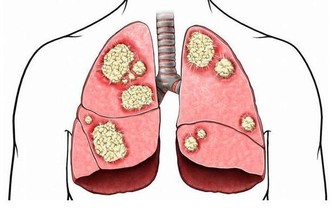

為預防“空調腿”的發生,空調溫度應以25℃~27℃為宜,也不要長期呆在空調房。

現在很多辦公室都是中央空調,溫度不受個人控制,工作需要又不能隨意離開。

建議對於這種情況,最好穿上長褲或者絲襪來保護膝關節,或在腿部蓋一條毛巾來防護。